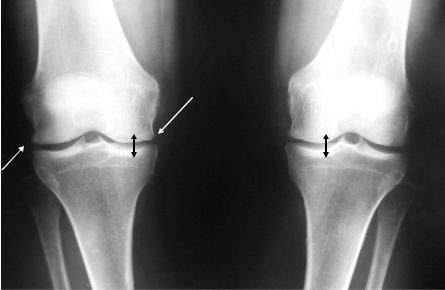

Основные рентгенологические признаки ОА: сужение суставной щели, остеофитоз, субхондральный остеосклероз (рис. 2-2) .

Рис. 2-2. Остеоартроз коленных суставов (3 ст. по Келлегрену).